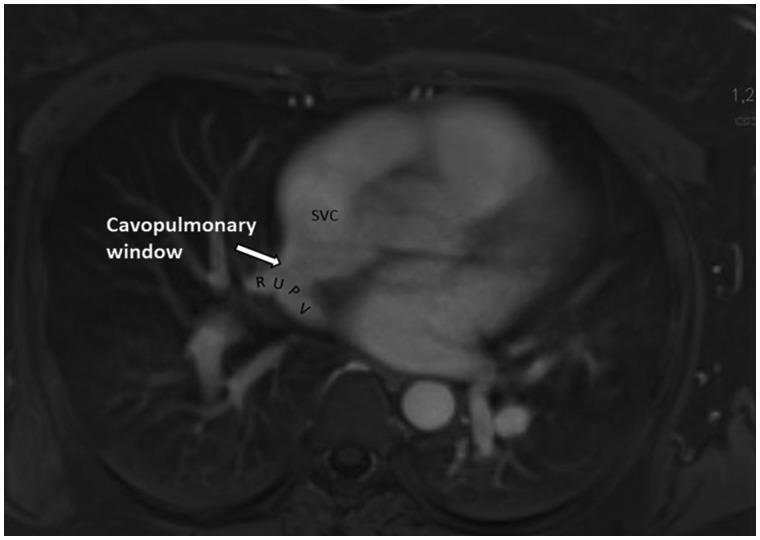

Isolated partial anomalous pulmonary venous return (PAPVR) with intact atrial septum is a rare finding. A cavopulmonary window is a side-to-side veno-venous communication of the right upper pulmonary vein with the superior vena cava which in its course retains connection to the left atrium.

We present a case of this unusual variant of a sinus venosus defect far from the atrial roof. Haemodynamic significance of the shunt was confirmed by enlargement of right heart cavities, elevation of pulmonary artery pressure, and significant left-to-right shunting using multimodality cardiac imaging (transoesophageal echocardiography, cardiac magnetic resonance imaging, and right heart catheterization). The defect has been successfully repaired using minimally invasive axillary thoracotomy.

孤立性部分性肺静脉异位引流(PAPVR)且房间隔完整是一种罕见的情况。腔肺窗是右上肺静脉与上腔静脉之间的左右侧静脉-静脉交通,其在走行过程中与左心房保持连接。

我们报告一例远离心房顶部的静脉窦型缺损的这种不寻常变异病例。通过多模态心脏成像(经食管超声心动图、心脏磁共振成像和右心导管检查)证实右心腔扩大、肺动脉压升高以及显著的左向右分流,从而确定了分流的血流动力学意义。该缺损已通过微创腋下开胸手术成功修复。